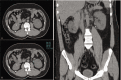

Patient concerns: A 32-year-old male patient diagnosed with congenital hemophilia A (FVIII = %4) with high responding inhibitors (7.4 BU) was admitted to our emergency department with gross hematuria and sudden onset flank pain.

Diagnosis: Abdominal computed tomography (CT-scan) presented a hyperdense lesion in the left ureteropelvic junction with Hounsfield Units of 56 compatibles with hemorrhage.

Outcomes: The patient's complaints disappeared on the fourth day of treatment. Macroscopic and microscopic hematuria was not seen in the following days. Follow-up CT was done 3 months after discharge and showed normal left renal pelvis without hyperdenosis. Follow-up CT was performed 3 months after discharge and presented normal left renal pelvis with no hyperdense lesion.